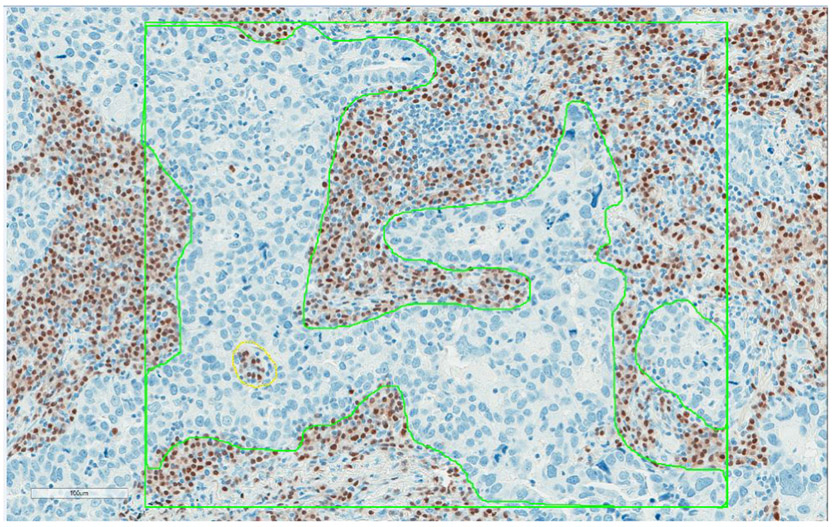

Methods: CD3, CD20 and MUM1 immunostains were performed on representative tumor blocks selected from 120 consecutive lung adenocarcinoma cases treated by surgical resection at Mayo Clinic Rochester. CD3+ T-cells, CD20+ B-cells, and MUM1+ plasma cells were enumerated separately in the intraepithelial (IE) compartment and the stroma (ST) by digital image analyses using whole sections. Measured tumor-infiltrating plasma cells and B-cells were correlated with patient's overall survival (OS) using Cox proportional hazards analysis.

Results: Median age of patients was 69 years (range, 46-91 years) and 52 were male. Median numbers (interquartile range) of CD20+ B-cells per 1mm2 of tumor area (IE plus ST) and IE compartment within tumor area were 590 (224-1276) and 101 (38-109), respectively; the corresponding numbers of MUM1+ plasma cells were 298 (180-605), and 67 (22-145), respectively. The proportion of MUM1+ plasma cell among all TILs (MUM1+ cells/[CD3+ cells +CD20+ cells+MUM1+ cells] × 100) ranged 1%-59% (median13%) in the tumor area and showed a significant association with OS by univariate Cox analysis (negative correlation with hazard ratio (HR)=12.50 [95% confidence interval (CI), 1.75-89.27]). There was a significant association between IE CD20+ B-cells and the patient's OS in univariate analysis (positive correlation with HR=0.81 [95% CI, 0.68-0.96]). Both parameters remained significant by multivariate analysis.

Conclusion: High plasma cell % among TILs in the tumor area and low IE B-cell count were associated with worse prognosis in lung adenocarcinoma patients.